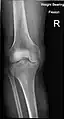

X-ray

Knee X-ray (weight bearing)